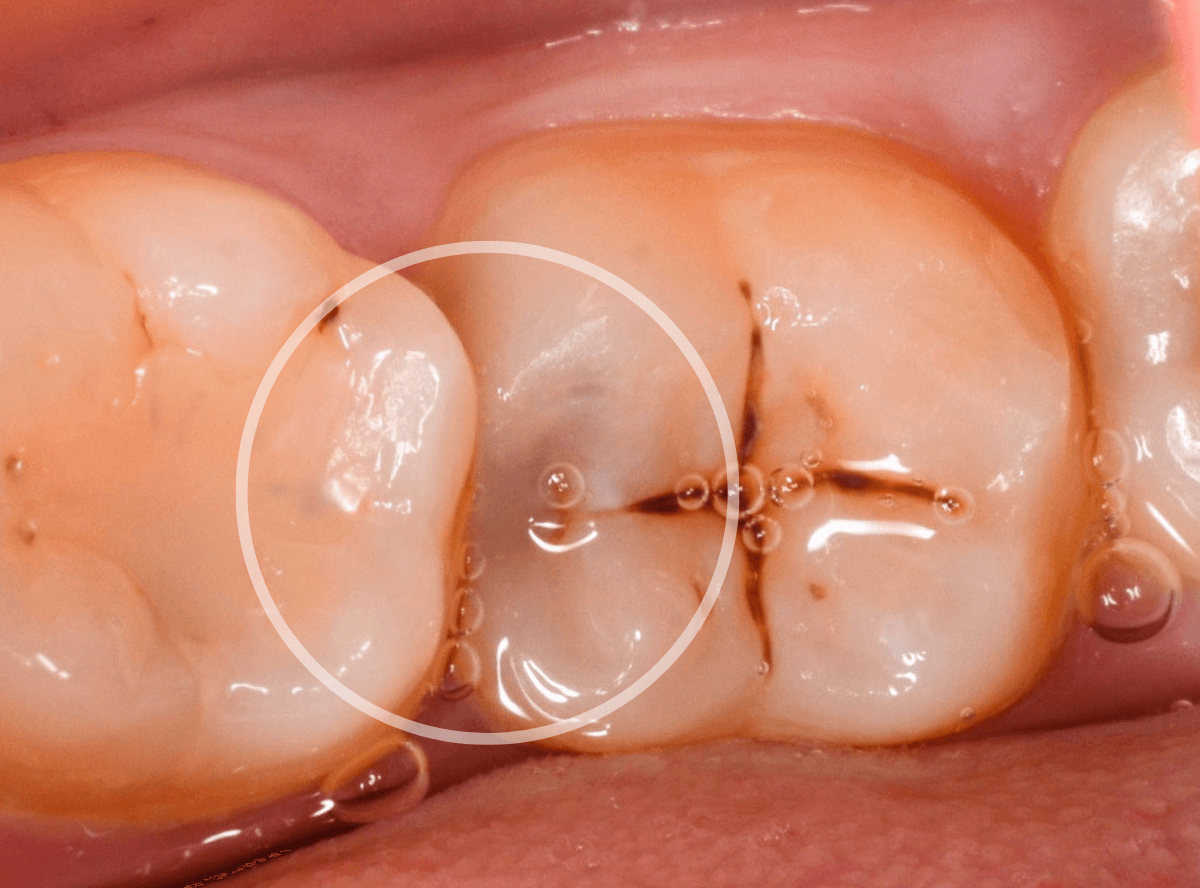

Case.10 レントゲンに写らない側面の虫歯を、少しずつ削って調べる

こちらも、虫歯が歯のあちこちで進行してしまっている患者さんのケースです。

特に側面の虫歯が深そうです。

側面にできた虫歯はレントゲン写真では診断しづらくやっかいです。

今回は「見るからに深そう」ですが。

さすがにレントゲン写真でも虫歯がありそうな事は確認できますが、実際にどうなってるのかはあまりはっきりわかりません。

少しずつ虫歯を除去していきます。

歯の側面から、手前の歯までつながった虫歯になっていました。

手前の歯までの虫歯を除去しました。

歯の後ろ側の側面も、大きな虫歯になっていますので、処置します。

隣の歯との間(隣接面)は、中で虫歯が広く進んでることが多いです。

結局、前後の歯に渡る広い虫歯でした。

レントゲン写真だけでは、ここまでの虫歯は判断できませんでした。